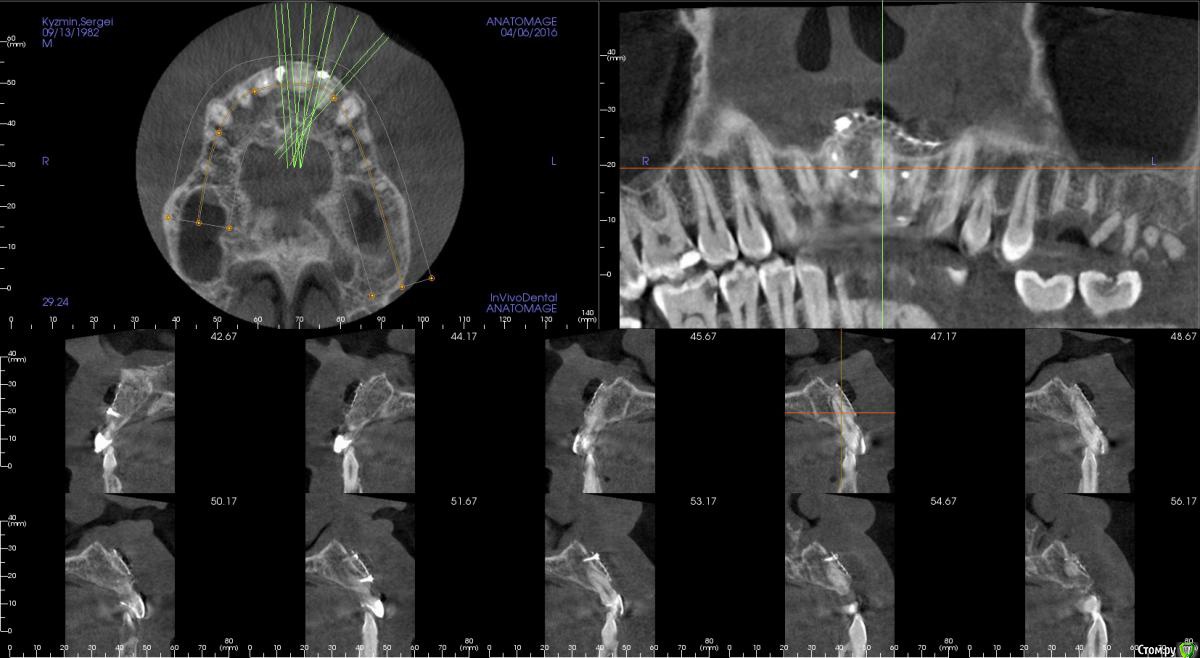

kamranchick Опубликовано 17 апреля, 2016 Поделиться Опубликовано 17 апреля, 2016 Пришел пациентДок привет, что то зуб шатается, можно ли его оставить, вот такие дела)как бы вы поступили бы? Ссылка на комментарий

dantist_movani Опубликовано 27 апреля, 2016 Поделиться Опубликовано 27 апреля, 2016 Пришел пациентДок привет, что то зуб шатается, можно ли его оставить, вот такие дела)как бы вы поступили бы?1)проверил бы на витальность2)Репозиция и шинирование орто ретейнером с жидкотекучим композитомпохожая ситуация была год назад, правда отлом кортикалки не столь значительный был. Ретейнер снял через 6 мес, все Ок, зуб не почернел♿, эод -8 в дуге, пац очень доволен Ссылка на комментарий